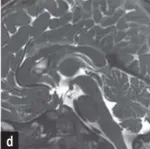

影像学检查显示基本正常,唯独存在一处细微异常。为明确诊断,如如接受了头颅核磁共振检查,但结果并未提供清晰答案,反而增加了医生的困惑。影像评估显示,如如的脑部结构与常人基本一致:中脑导水管形态正常,脑脊液流动未见梗阻,侧脑室宽度也在标准范围内。然而,医生注意到一个细微的异常征象——导水管入口处存在明显狭窄。这一发现究竟提示何种疾病?遗憾的是,尽管识别出这一结构性异常,但结合如如的整体临床表现,多种最初怀疑的疾病可能性都被逐一排除。

这是否意味着所有松果体囊肿都需要手术治疗?在一定程度上,答案是否定的。传统的手术指征通常仅限于囊肿体积增大,引发脑室扩张并导致脑积水的情况。然而,如如的术前临床表现并不符合这一传统标准,她并未出现脑积水征象。那么,施罗德教授决定实施手术的依据何在?在其研究论文《Symptomatic Pineal Cysts Without Ventricular Enlargement》中,施罗德教授明确指出,对于未伴发脑室扩张的症状性松果体囊肿,手术决策需审慎权衡患者的整体状况。既要避免过度手术治疗,也不能因诊断不足而忽视患者的痛苦。因此,他建议当患者出现颅内高压临床表现(如剧烈全头痛、喷射性呕吐)、脑干受压体征,且磁共振成像证实囊肿存在占位效应或导致导水管狭窄时,应及时考虑手术治疗。